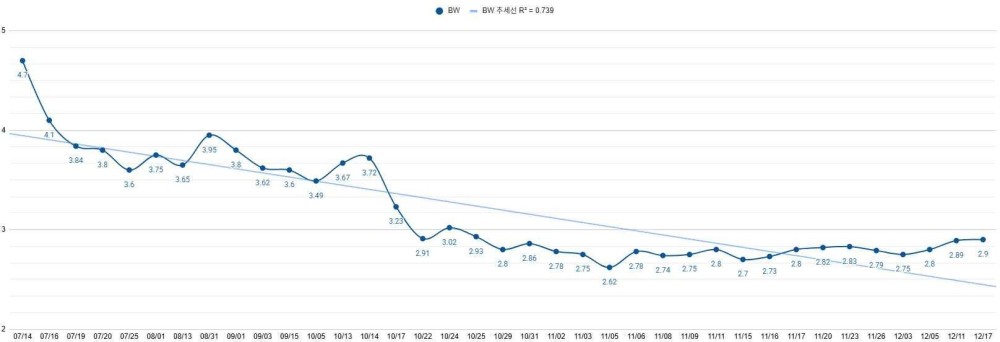

오늘은 반복되는 설사와 체중 감소, 복수와 저알부민혈증으로 장기간의 진료와 관리가 필요했던 비숑프리제 강아지 ‘나무’의 치료 과정을 소개해 드리겠습니다.

병원 내 기본 검사 결과, 체중은 4.7kg이었고 체온은 38.4℃로 비교적 안정적이었으나, 심박수와 혈압은 다소 높은 편이었습니다. 만성 장 질환의 중증도를 평가하는 지표인 CCECAI 점수는 13점으로, 중등도 이상의 만성 장 질환이 의심되는 상태였습니다.

체중 감소는 있었으나 전반적인 컨디션을 고려해 스테로이드 감량(tapering) 을 조심스럽게 시작했습니다.

체중은 3.65kg으로, 이전 방문 대비 소폭 회복된 모습을 보였습니다. 체온은 39.3℃로 유지되었고, 심박수는 124회/분, 호흡수는 48회/분으로 측정되었습니다. 혈압은 168mmHg로 다소 높게 확인되었습니다.

10월 초부터는 체중 감소와 함께 장 증상이 반복되며 장기 관리 단계로 접어들었습니다.

[체중 변화]